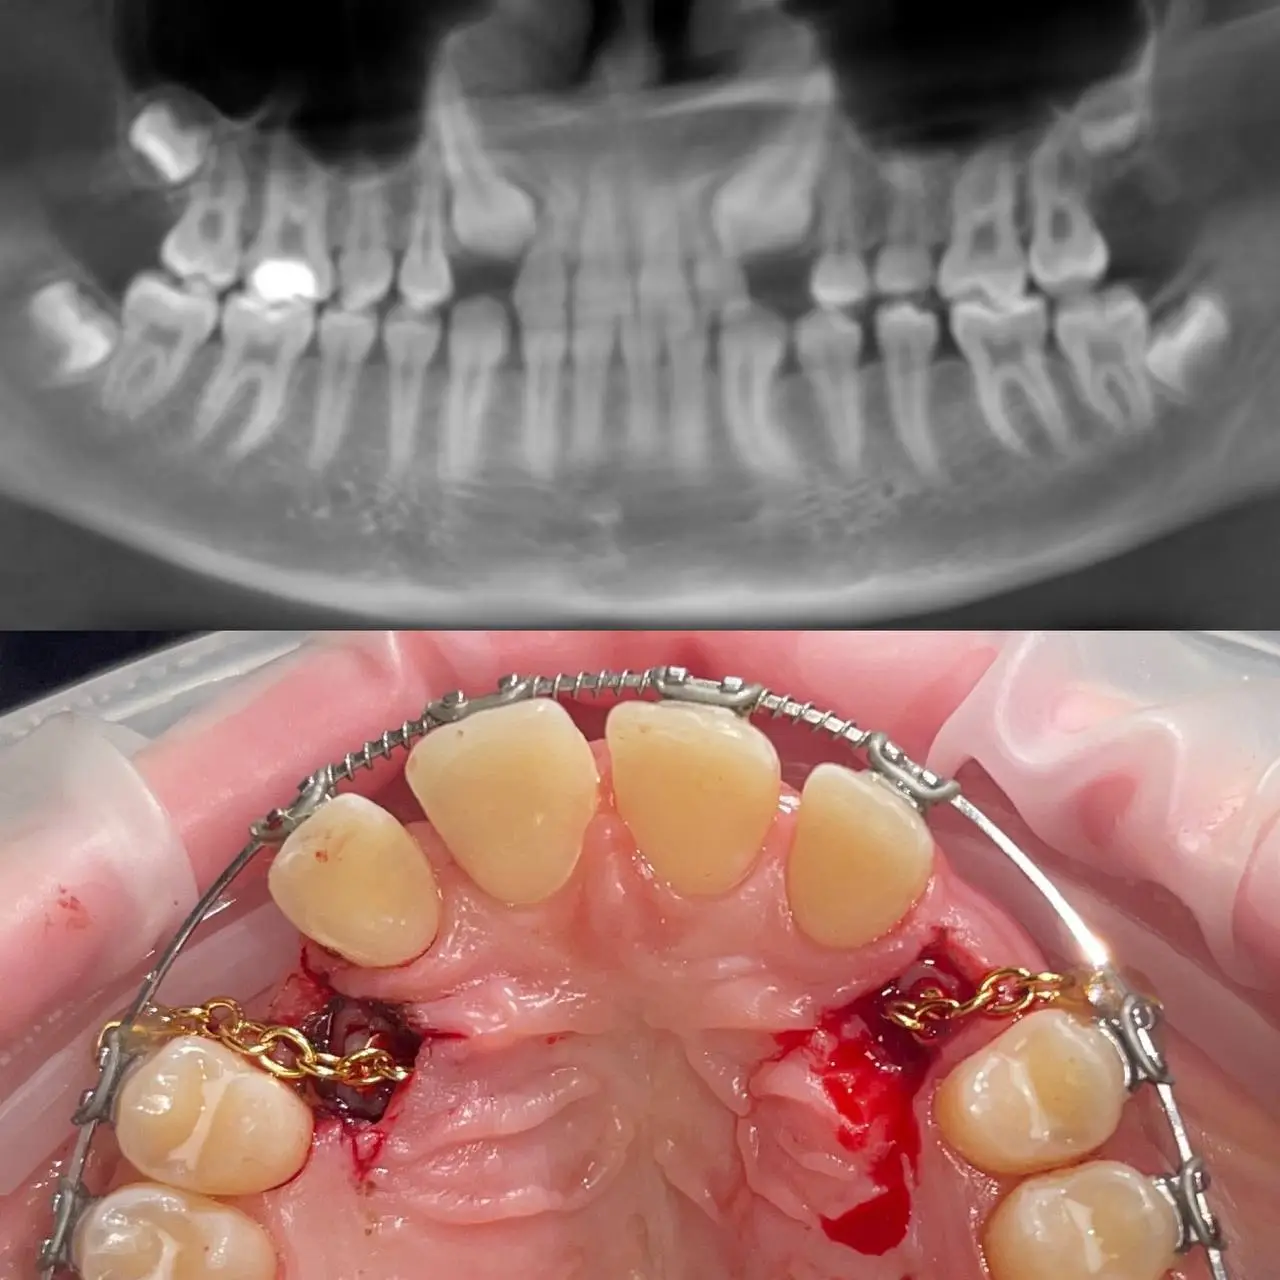

На піднижньощелепні камені припадає від 80 до 92 відсотків усіх випадків сіалолітіазу, тоді як на привушні камені припадає більшість решти випадків (6–20 відсотків). Під’язикові та малі залози мають відносно низький ризик розвитку каменів. Більшість каменів утворюється лише в одній залозі, але можливе утворення кількох каменів одночасно. Маленькі камені, які не блокують відтік слини, можуть виділятись без симптомів. Однак, коли потік слини стає повністю заблокованим, це може призвести до інфікування відповідної слинної залози Симптоми сіалолітіазу Симптоми зазвичай виникають, коли ви намагаєтеся поїсти (оскільки саме тоді стимулюється виділення слини) і можуть зникати протягом кількох годин після їжі або спроби поїсти. Про це важливо повідомити свого лікаря, оскільки це може допомогти відрізнити сіалолітіаз від інших захворювань.